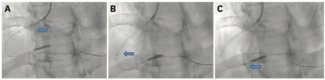

This is a retrospective analysis of consecutive patients treated with IVL for coronary calcification using the C2+ Shockwave balloon from its implementation in November 2022 through December 2023, with comparison to consecutive patients in...